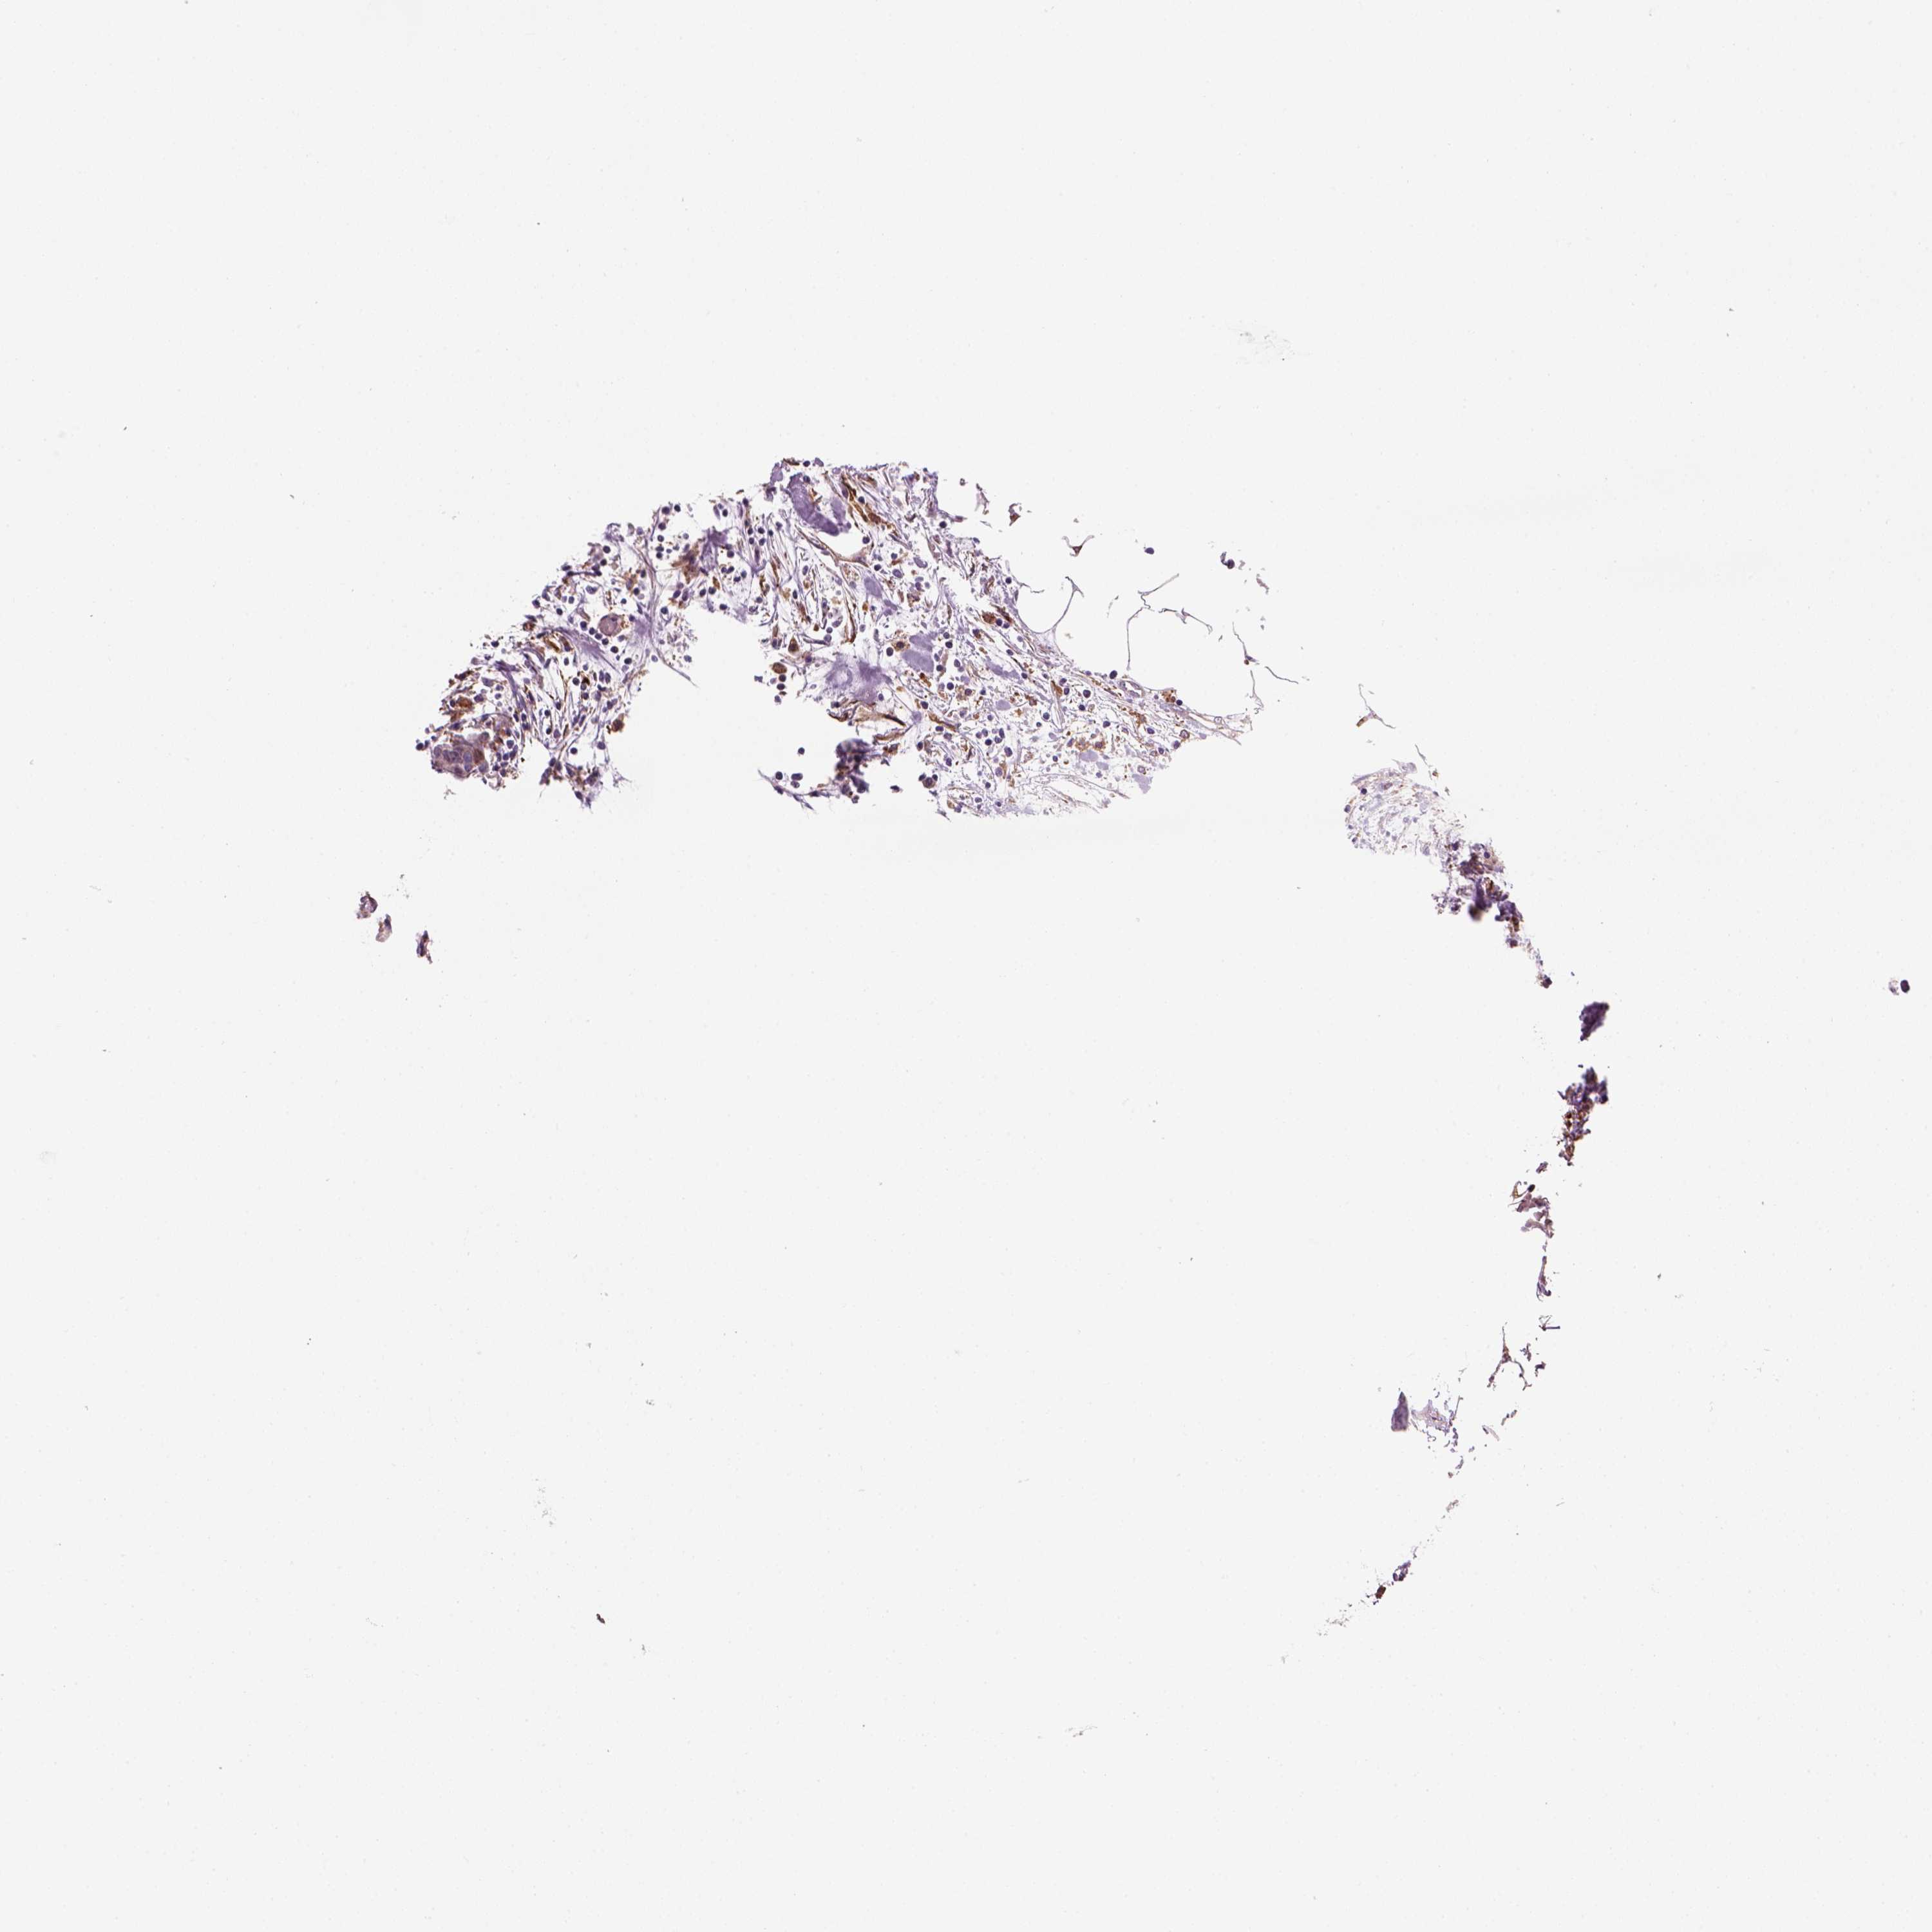

CARCINOID - Protein expressioni

A mouse-over function shows sample information and annotation data. Click on an image to view it in a full screen mode. Samples can be filtered based on level of antibody staining by selecting one or several of the following categories: high, medium, low and not detected. The assay and annotation is described here.

Each image is clickable and will lead to virtual microscopy that enables deeper exploration of all samples and also displays staining intensity scores, fraction scores and subcellular localization as well as patient and tissue information for each sample.

Antibody HPA067595

Antibody HPA069443

Antibody CAB022062

Carcinoid, malignant, NOS